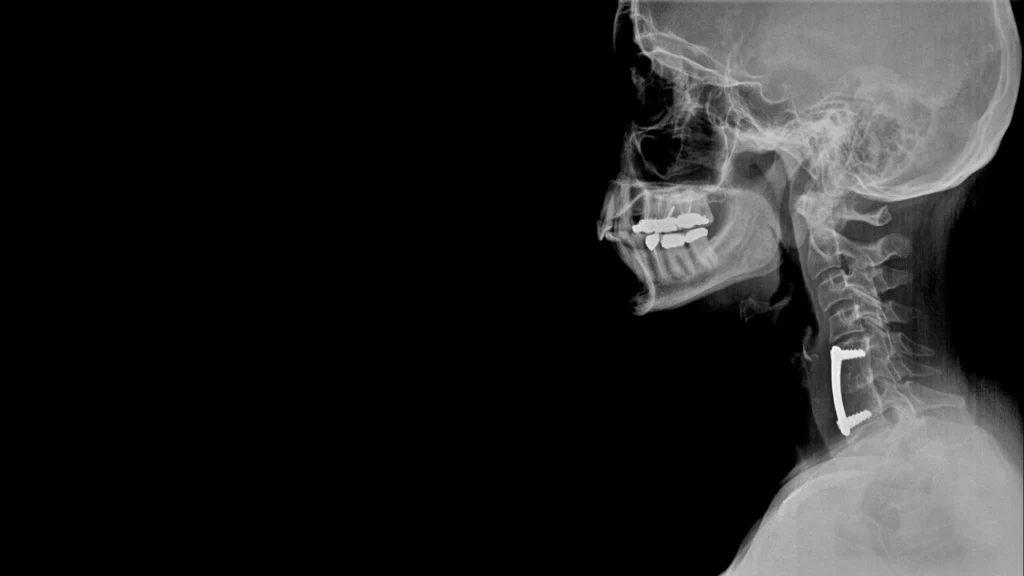

While fusions in the past were regularly performed via a large incision, or an “open surgery”, advances in technology and technique have made it possible for spinal fusions to be performed through less invasive techniques under general anesthesia. This means that surgeons make small incisions near the affected vertebrae. Special instruments are used to access the surgical site through these incisions. This decreases the degree of muscle disruption that can result in increased postoperative pain and lengthy recovery times. The fusion surgery itself involves implantation of bone grafts and instrumentation, such as screws and rods, to span the space between two or more vertebra. As the grafts heal, a solid column of bone develops that provides stability to that portion of the spine.